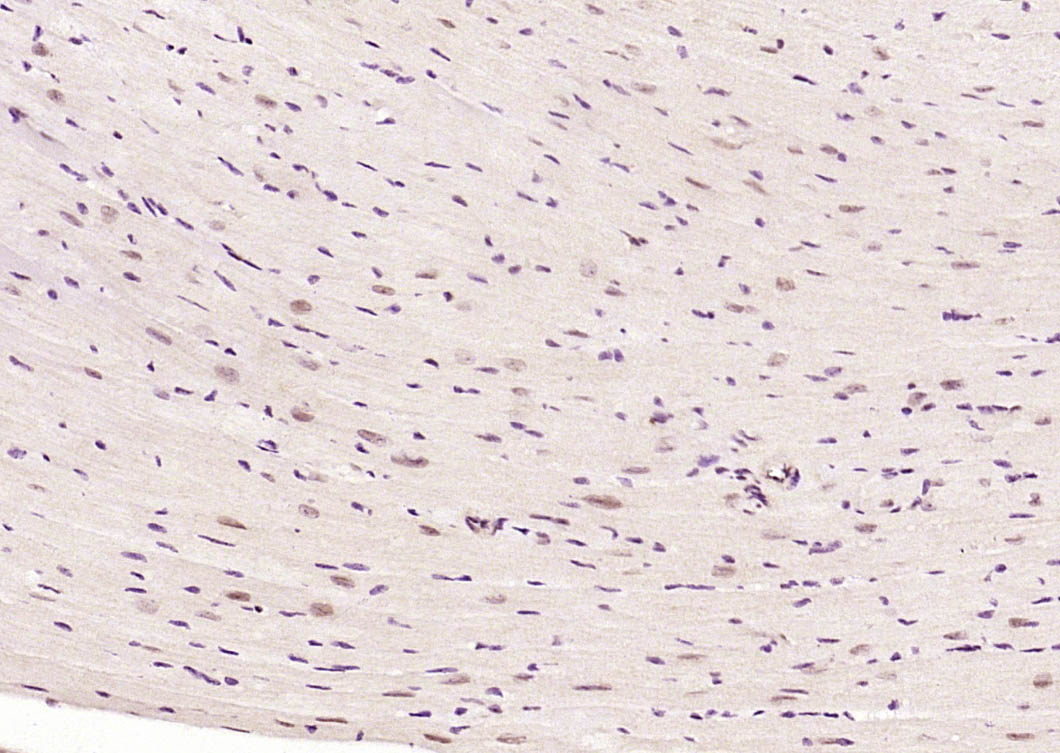

| IHC-P | Human, Mouse | Rat | 1:100-500 |